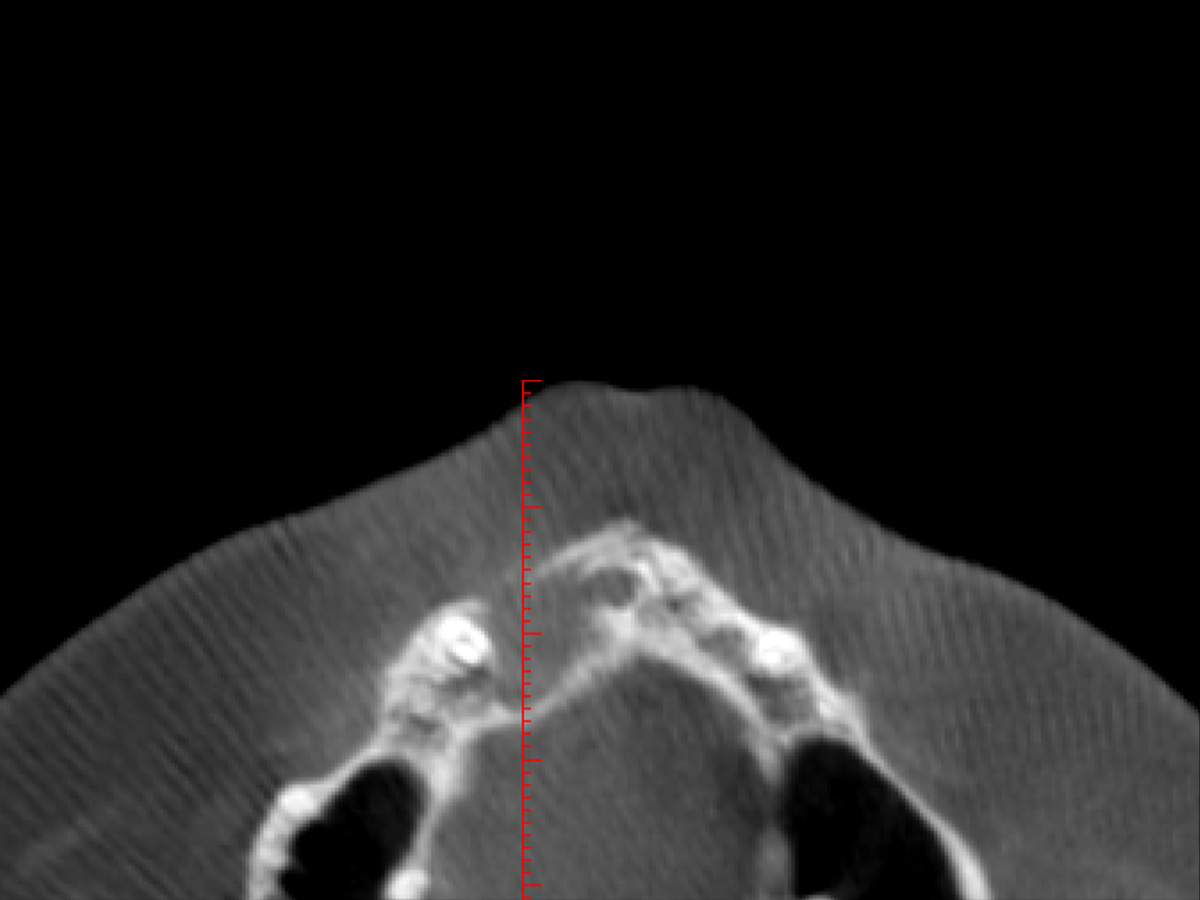

Abbildung 5

Im DVT ist eine große zystische Formation unter Einschluss der Wurzeln 11 und 12, die vom Canalis nasopalatinus...

Abbildung 6

...bis mesial 13 mit einer kleineren Perforation zum Nasenboden...

Abbildung 7

...und größeren Perforationen nach vestibulär und palatinal reicht.

Nach einem Zahntrauma im Jugendalter mit anschließender endodontischer Versorgung stellte sich unsere 24-jährige Patientin mit seit einigen Monaten bestehendem, rezidivierendem Druckgefühl und leichten Schmerzen in regio 11 und 12 vor (Abb. 1, 2, 3). Die klinische Untersuchung ergab an Zahn 11 und 12 Lockerungsgrad 1 und, wie zu erwarten, eine negative Sensitivität. Es lag ein leichter Perkussionsschmerz vertikal wie horizontal vor. Die Krone auf Position 11 zeigte eine leichte Verfärbung im Vergleich zu den Nachbarzähnen. Ein OPG ergab eine – in ihrer Ausdehnung nicht sicher zu beurteilende – Aufhellung im Knochenbereich regio 11 und 12 (Abb. 4). Als Nebenbefund waren teilretinierte Zähne 38 und 48 sowie ein vollständig retinierter Zahn 28 als Mikroform nachzuweisen. Ein zusätzlich durchgeführtes DVT zeigte eine große zystische Formation unter Einschluss der Wurzeln 11 und 12, die vom Canalis nasopalatinus bis mesial 13 mit einer kleineren Perforation zum Nasenboden und größeren Perforationen nach vestibulär und palatinal reichte (Abb. 5, 6, 7).